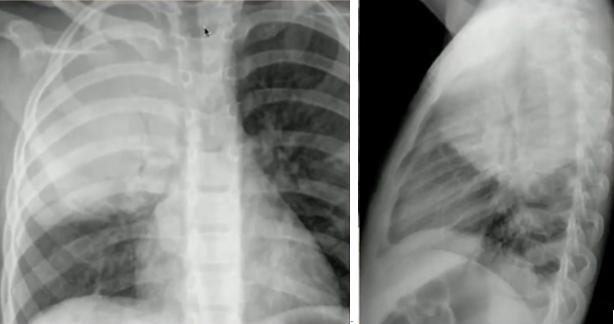

图14.“脊柱征”:位于心影后的下叶肺炎在正位片中不易看出,侧位片中可表现为椎体变白

正常侧位片(左)与下叶肺炎(右)